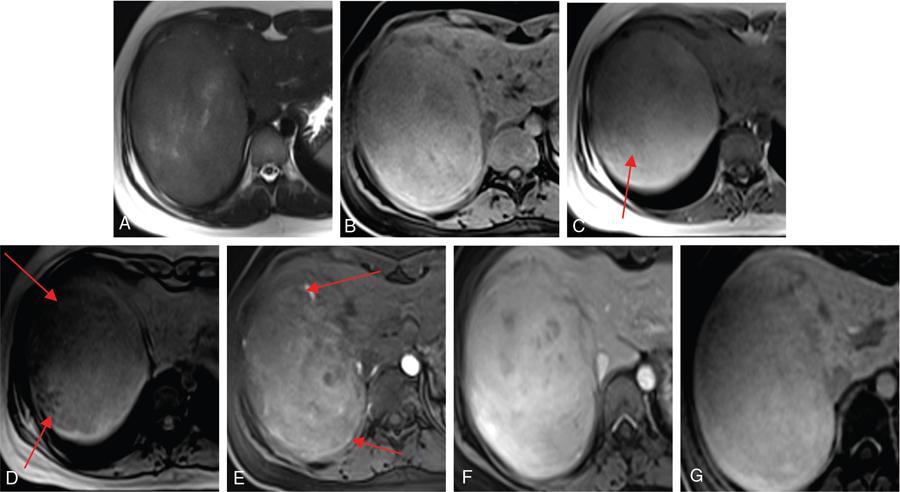

Ritu K. Kashikar, Shrinivas B. Desai, Pooja Punjani Vyas, Nilesh Doctor, Vivek Shetty Owing to advances in technology, focal liver lesions (FLLs) are increasingly encountered. Imaging particularly computed tomography (CT) and magnetic resonance imaging (MRI) play a vital role in diagnosis and characterization of FLL, thus avoiding unnecessary biopsies and interventions. Multiphase CT accurately diagnosis most liver lesions. Better soft tissue contrast and lack of ionizing radiation makes MRI a preferred modality in diagnosing FLLs. MRI with or without contrast for characterization of liver lesions regardless of preexisting liver disease has been assigned the highest rating as per American College of Radiology Appropriateness Criteria (Table 9.11.1). Solid lesions of epithelial origin Solid lesions of nonepithelial origin Pitfalls Cystic liver lesion Developmental cyst Infective cyst Miscellaneous Tmours of hepatocellular origin Tumours of nonepithelial origin Malignant cystic lesion Hepatic metastasis Ultrasound is often the initial modality for diagnosis and also the incidental detection of FLLs. Limitations to USG include the detection of small lesions less than 2 cm in size, particularly in patients who are cirrhotic or undergoing chemotherapy. Characterization of FLLs, involvement of crucial structures such as blood vessels, local staging and decisions such as operability are also not accurate with ultrasound alone and require confirmation with CT/MRI. The liver typically images in supine and left lateral positions. A curvilinear transducer with a frequency of 1.5 Hz is used. The subcostal diagonal, subcostal longitudinal or sagittal and transverse right intercostal lateral views are used. Right lobe of liver is imaged through an intercostal approach when the patient is taking deep inspiration. Subcostal view is used to image the three hepatic veins in one view. Transverse, longitudinal and oblique views of the liver are taken to image all the segments of liver. Colour and power Doppler have increased sensitivity for FLL detection, but sensitivity is still inferior to contrast-enhanced CT and MRI. The introduction of microbubble contrast agents (CAs) and the development of contrast-specific techniques have opened new perspectives in ultrasound of the liver. The technique is based on a new class of intravascular microbubble agents which contain perfluoro gases instead of air. This when combined with scanning modes sensitive to harmonic responses of microbubbles enable tissue signal suppression. The advent of the multislice technique and isotropic voxel have improved the spatial resolution of CT, allowing the recognition of small FLLs in difficult areas. Multislice CT has a sensitivity and specificity in the diagnosis of malignant FLLs of 63% and 64%, and 92 and 97%, respectively. Contrast media administration with dose based on the patient’s weight (approximately 600 mg iodine/kg of bodyweight), an iodine content of 350–400 mg/mL and a high injection rate of 4–5 mL/s are imperative to attain good contrast enhancement. Region of interest in the abdominal aorta and a threshold of 100 HU allows correct timing for threshold. A delay of approximately 18 s after the threshold provides the first arterial phase, allowing detection of hypervascular FLLs such as hepatocellular carcinoma (HCC). The late arterial phase is obtained approximately 10 s after the early arterial phase and shows progressive enhancement of hypervascular lesions, improving detection rate, while the optimal hepatic enhancement in the portal phase is reached approximately 50–60 s after the threshold. Portal venous thrombi are also best detected in this phase. The venous phase aids in the detection of washout, hepatic venous thrombosis. Delayed phase is often required in lesions such as cholangiocarcinoma and haemangioma, which show progressive enhancement (Table 9.11.2, Fig. 9.11.1). Delayed phase images are required for tumours such as cholangiocarcinoma and large haemangiomas, which reveal delayed enhancement. As mentioned previously, MRI is the modality of choice in diagnosis of FLLs. Most FLLs appear hyperintense on T2W1 images with varying intensity depending upon the water content and flow dynamics. FLLs are typically hypointense on T1W1 images with the exception of fat containing, haemorrhagic lesions and those containing chelates of metals like regenerating/dysplastic nodules. In- and opposed-phase images help in detection of intralesional fat. Diffusion-weighted images are beneficial particularly in noncirrhotic population and best suited in detection of metastasis. Postcontrast images obtained with extracellular agents are parallel to those obtained with CT (Fig. 9.11.2). The pre- and postcontrast MRI protocol is mentioned in Table 9.11.3. T2-weighted single-shot fast spin-echo (SE) T1-weighted in- and opposed-phase GRE Dynamic 3D T1-weighted FS spoiled GRE (in hepatic arterial, portal venous and equilibrium phases) There are two main categories of CAs used in liver imaging – the extracellular and the hepatocyte-specific (Fig. 9.11.3). Extracellular agents are more widely used and provide information similar to contrast-enhanced CT study. The advantage of the other category of CAs, that is, hepatocyte-specific agents, is the ability to provide this extracellular information with added benefit of delayed phase information. Tumours of hepatocellular origin with functioning hepatocytes take up and biliary excretion with take up and retain these agents appearing isointense to background liver. Lesions without functioning hepatocytes fail to retain contrast and hence appear hypointense to background liver on delayed phase. This allows better detection and characterization of focal liver lesion particularly those lesser than 2 cm (Table 9.11.4). Haemangioma is the most common benign hepatic tumour. The incidence in general population varies from 1% to 20%. Females have a higher preponderance with variable female to male ratios of 2:1 to 5:1. Imaging in particular MRI has high reliability in diagnosing classic haemangioma. The sensitivity and specificity of MRI is greater than 90% in diagnosis. The aetiology of haemangioma is unknown. Since haemangiomas are known to run in families, a genetic origin has been implicated, while other mesenchymal tumours are thought to be congenital. Most patients are asymptomatic and often the lesion is discovered as an incidental finding. Pain in the right upper abdomen is the most common complaint; others include loss of appetite, nausea, vomiting and abdominal discomfort. Symptoms are usually seen in large haemangiomas or those with complications. Liver function tests and tumour markers like AFP and CA19.9 are within normal limits. Blood-filled cavities of varying sizes lined by flat endothelial cells and supported by fibrous connective tissue are seen on histology. Three histological subtypes have been described: the capillary haemangioma, the cavernous haemangioma and the sclerosing haemangioma. The imaging features of a haemangioma depend on its size; typical haemangiomas are mostly less than 3 cm in diameter. Haemangiomas are hyperechogenic, homogeneous lesion presenting a posterior acoustic enhancement (Fig. 9.11.3). The hyperechogenicity of haemangiomas is related to the interfaces between vascular spaces, fibrous stroma and the slow blood flow. Typically, haemangiomas have slow flow and hence do not show vascularity on colour or power Doppler. The sensitivity and specificity of ultrasound in differentiating haemangioma from other malignant lesions are high, with values of approximately 94.1% and 80%, respectively, for lesions less than 3 cm in diameter. Unlike HCC, no flow is seen on colour Doppler. A peripheral echogenic rim around hypoechoic lesions can suggest haemangioma. On the contrary, perilesional hypoechoic rim called the target sign is seen in lesions such as metastasis (Table 9.11.5). Adenomas can be distinguished on the basis of the absence of posterior acoustic enhancement and characteristic pattern of peripheral vascularity seen in adenoma. Another differential diagnosis to be considered is focal nodular hyperplasia (FNH), which has the characteristic ‘spoke-wheel sign’. Contrast-enhanced ultrasound (CEUS) improves specificity for the diagnosis of haemangioma. The vascularity pattern with contrast-enhanced USG is similar to that seen with CT. The typical hemangioma (HH) shows peripheral nodular enhancement in the arterial phase with complete (but sometimes incomplete) centripetal filling in the portal venous and late phases. This particular pattern of enhancement helps in differentiating haemangiomas from other lesions like adenomas, FNH, HCC or metastasis. This characteristic enhancement pattern has a sensitivity of 98% for histologically proven HH. One should be aware that an HH can rarely have a centrifugal enhancement. Computed tomographic (CT) findings consist of a hypoattenuating lesion on nonenhanced images. Haemangiomas show peripheral discontinuous nodular enhancement on arterial phase of dynamic contrast-enhanced CT. The density of the nodules is equivalent to that of the aorta. Centripetal filling with is seen on venous phase, which progresses to uniform enhancement. The enhancement persists on delayed phase (Fig. 9.11.4). Washout of contrast on delayed phase is not seen in haemangioma and if seen, alternate diagnosis must be considered. This classical pattern of enhancement cannot be highlighted in very small lesions of less than 5 mm, which can be difficult to characterize. In patients with severe fatty infiltration of the liver, HH can appear hyperdense relative to the adjacent liver parenchyma on nonenhanced scan. Haemangiomas are hyperintense on T2-weighted images, which is identical to that of cerebrospinal fluid. T2 hyperintense signal is classically described as ‘light bulb bright’. Malignant lesions of the liver do not appear as bright on T2W1 images. They appear hypointense to adjacent liver on T1-weighted images. Long relaxation T2W1 images further improve accuracy in diagnosis of haemangiomas and help in differentiation from metastasis. Haemangiomas, unlike other liver lesions retain hyperintense signal on long relaxation T2W1 images. A threshold of 112 ms has 92% accuracy, 96% sensitivity and 87% specificity for differentiating haemangiomas from metastasis. On gadolinium administration, the enhancement pattern is similar to that seen with iodinated contrast on CT. Classic enhancement pattern in combination with characteristic T2 appearance are diagnostic for haemangioma (Fig. 9.11.5). Certain pitfalls exist in diagnosing haemangiomas using gadoxetate disodium. Due to the lack of hepatocytes, haemangiomas appear hypointense to the background liver on delayed hepatocyte phase and mimicking malignant process (Table 9.11.6). Lesions shown peripheral nodular arterial enhancement (Table 9.11.7): On fluorodeoxyglucose-positron emission tomography (FDG-PET)/CT, most hepatic haemangiomas appear low-attenuation lesions with FDG avidity equal to background liver parenchyma and are easily determined to be benign. However, a small percentage of haemangiomas may be FDG-avid. If an FDG-avid hepatic lesion demonstrates the characteristic enhancement pattern, this is consistent with an FDG-avid haemangioma. Technetium-99m pertechnetate-labelled red blood cell scintigraphy has high specificity in the diagnosis of haemangiomas. In this technique, there is decreased activity in haemangiomas on early images and increased activity on delayed blood pool images. Therefore, radionuclide scintigraphy has a sensitivity of 78% and an accuracy of 80% and may be a valuable tool when the diagnosis cannot be achieved with other imaging modalities. Large haemangiomas are often heterogeneous with internal clefts and septae. They are termed as giant haemangiomas when they exceed 4 cm in diameter. Discrepancies are there in definition with some authors defining giant haemangiomas as lesions greater than 6 cm or 12 cm in diameter. These may cause symptoms of abdominal pain and distension. These haemangiomas demonstrate changes such as haemorrhage, thrombosis, extensive hyalinization, liquefaction and fibrosis. The central cleft-like area may be due to cystic degeneration or liquefaction. On USG, they reveal heterogeneous echotexture. They are hypoattenuating and heterogeneous on nonenhanced CT with central areas of low attenuation. After intravenous administration of contrast material, the typical early, peripheral and globular enhancement is observed. These may show irregular or ‘flame-shaped’ discontinuous peripheral enhancement as opposed to typical nodular enhancement pattern seen in smaller haemangiomas. Although centripetal pattern of enhancement is seen during the venous and delayed phases, the filling-in incomplete. Central scars are defined in this subset of haemangiomas (Fig. 9.11.6). At MRI, T2-weighted images show a markedly hyperintense cleft-like area and some hypointense internal septa within a hyperintense mass. On delayed phase, incomplete filling and central scar are seen similar to CT (Fig. 9.11.7). Complications include intratumoural haemorrhage, inflammatory changes or consumptive coagulopathy (Kasabach–Merritt syndrome). These may warrant management such as arterial embolization or resection. This pattern is seen 16% of all haemangiomas, and is seen more often in small haemangiomas (42% of haemangiomas) <1 cm in diameter. CT and MRI show immediate homogeneous enhancement at arterial phase CT or contrast-enhanced MRI. The size of the blood spaces is the reason for difference in enhancement pattern. Smaller the lesion, smaller the size of blood spaces and faster the rate of spread of contrast material. These lesions usually show perilesional halo of hyperenhancement on the late arterial phase, which is believed to be due to arteriovenous shunting. Rapid arterial enhancement makes these haemangiomas difficult to distinguish from hypervascular metastasis (Table 9.11.8). However, washout of contrast is seen from haemangiomas on delayed phase (Fig. 9.11.8). Hepatic haemangiomas rarely demonstrate calcifications, while haemangiomas in other locations frequently demonstrate phleboliths. Calcified haemangiomas are mostly found incidentally. Calcifications may occur in the marginal or central portion of the lesion and consists of multiple spotty calcifications, which correspond to phleboliths. However, large, organized calcifications are also possible. Some calcified haemangiomas may demonstrate poor enhancement. Hyalinized hepatic haemangiomas are rare. It has been suggested that hyalinization represents an end stage of haemangioma evolution. These haemangiomas are usually asymptomatic. The radiological features of a haemangioma are completely altered ones hyalinization occurs; hence biopsy is often mandatory for diagnosis. Hyalinized haemangiomas show only slight high signal intensity on T2W1 images. There is lack of early enhancement on dynamic contrast-enhanced images (Fig. 9.11.9). Fluid–fluid levels within haemangiomas are very rare. Fluid–fluid levels are seen both with CT and MRI with inferior layer representing the red blood cells and superior layer unclotted serous blood. Dependent hyperdensity/T1 hyperintensities can be seen corresponding with dependent haemorrhage. Pedunculated haemangiomas are very rare. They can be asymptomatic or complicated by subacute torsion and infarction. Typical enhancement pattern and signal on T1 and T2W1 images are clues to the diagnosis. Capsular retraction is usually associated with malignant tumours such as cholangiocarcinoma, epithelioid haemangioendothelioma or metastases. Rarely, it has been seen in haemangiomas. A possible mechanism could be fibrous degeneration. Multiple haemangiomas are seen in 10% of cases and usually show classical imaging features. Fatty infiltration of liver may alter the imaging appearances of lesions. Haemangiomas appear slightly hyperechoic, isoechoic or hypoechoic relative to the fatty liver. At nonenhanced CT, the lesion may be hyperattenuating relative to the liver. Contrast-enhanced CT shows peripheral enhancement and delayed filling, an appearance similar to that of a haemangioma in a normal liver. Haemangiomas are less common in setting of cirrhosis and may be difficult to diagnose due to sclerosis. Complications are seen in 4.5%–19.7% and often seen in large lesions such as inflammation, coagulation within can lead to systemic disorders, haemorrhage would lead to haemoperitoneum, volvulus and adjacent organ compression. Irrespective of the size, treatment is indicated only for haemangiomas with significant symptoms, those developing complications, or when there is an inability to exclude malignancy. Attempt should be made to exclude other causes of the patient’s symptoms. The term focal nodular hyperplasia (FNH) was introduced in 1958 by Edmondson. In 1995, the International Working Party classified FNH with other regenerative lesions, and not a neoplastic lesion. It is defined as a nodule consisting of normal appearing hepatocytes occurring in a histologically normal liver. It is the second most common tumour of the liver after haemangioma with a reported prevalence of 0.9%. The lesion is more commonly seen in females with female to male ratio of 8:1. Multiplicity is seen in 20% of patients. The combination of multiple FNH lesions and haemangiomas is considered to be multiple FNH syndrome. Vascular malformation and vascular injury have been suggested as the underlying mechanism. An association with steroids has been denied more recently. FNH has been classified as classic and nonclassic varieties. These have been discussed in Table 9.11.9. Classic FNH is characterized by abnormal nodular architecture, malformed vessels and cholangiolar proliferation. Nonclassic FNH lesions lack one of the following classic features – nodular abnormal architecture or malformed vessels – but always show bile ductular proliferation. Classic FNH on gross appearance shows lobulated contours with multiple nodules surrounded by fibrous septae originating from a central scar, which contains a vascular malformation. On histopathology, nodular hyperplastic parenchyma is seen in classic FNH. Circular or short fibrous septae surround these nodules completely or incompletely. Thickening of the hepatic plates is seen. Fibrous connective tissue, cholangiolar proliferation with surrounding inflammatory infiltrates and malformed arteries, capillaries, vascular channels of undetermined type and veins are seen in the central scar. The arterial blood in FNH shows centrifugal distribution from anomalous central arteries. Fatty infiltration is seen in approximately 50% of lesions, while signs of hepatic steatosis are seen in approximately 20% of cases with classic FNH. Variable amounts of Kupffer cells are seen in both classic and nonclassic variants. Nonclassic FNH is heterogeneous and on gross appearance resembles adenomas in most cases, with vaguely lobulated contours and lack of a macroscopic central scar. The histology varies with subtypes. Subtypes of nonclassic FNH include telangiectatic type, mixed hyperplastic and adenomatous forms and FNH with cytologic atypia. The histological features of these are described in Table 9.11.10. At US, typical FNH is often not well visualized. The lesions may be slightly hypoechoic, isoechoic or slightly hyperechoic. The compressed liver tissue form a hypoechoic halo around the lesion, which appears more prominent in patients with fatty infiltration. A prominent central scar may improve the conspicuity of the lesions. Use of colour and power Doppler US shows vascularity in suspected FNH. On contrast-enhanced USG, FNH is hyperenhancing in the arterial and portal venous phases in more than 90% of cases. The arterial enhancement patterns include central (60%–70% of cases) or eccentric (<20% of cases) with centrifugal filling, but sometimes are homogeneous. Multiphase CT is an excellent modality for detection and characterization of FNH. These lesions classically show a lobulated contour. At unenhanced CT, the lesions are either hypoattenuating or isoattenuating to the surrounding liver. In the arterial phase, the lesions show homogeneous intense enhancement except the central scar and fibrous septa. In the portal and later phases, the lesions become more isoattenuating with the surrounding liver. The central scar reveals enhancement on delayed phase (Fig. 9.11.10). This feature helps distinguish from other lesions with central scar-like fibrolamellar carcinoma. A vascular malformation can be seen in the central scar in some cases (Fig. 9.11.11). There may be enlarged hepatic veins in the vicinity of the mass. FNH do not have portal venous drainage. The drainage is essentially into hepatic venules, hence the enlarged adjacent veins. The central scar is often not identified in small FNH lesions. In a study, 80% of FNH lesions less than 3 cm lacked visible central scar. The sensitivity and specificity of MRI in diagnosis of FNH are 70% and 98%, respectively. The central scar is more often detected with MRI than with CT (78% and 60%, respectively). FNH is typically iso- or hypointense on T1-weighted images (94%–100%) and is slightly hyperintense or isointense on T2-weighted images (94%–100%). The lesions may not be very conspicuous on T2W1 images. The central scar is hyperintense on T2-weighted images in 84% of cases. FNH shows intense homogeneous enhancement in the arterial phase. The enhancement pattern in arterial phase may be nodular, resembling a popcorn, the result of intralesional fibrous septae. Mosaic pattern of heterogeneous enhancement seen in malignant lesions is not seen in FNH. Central vascular malformation may be seen in early phases. These lesions classically fade to isointensity on delayed phase with the exception of the central scar (Fig. 9.11.12). FNH may show a pseudocapsule, which results from compression of the surrounding liver parenchyma by the FNH, perilesional vessels and inflammatory reaction. The pseudocapsule may show enhancement on delayed contrast-enhanced images. A central scar is present at imaging in most patients with FNH. The central scar is hyperintense on T2W1 and hypointense on T1W1 images. The presence of inflammation and vessels within the scar are responsible for the hyperintense signal (Fig. 9.11.13). The scar does not enhance on early phases of contrast study and shows enhancement on delayed phases of dynamic study. The scar is absent in 30% of cases. The hepatocyte-specific CA gadoxetate disodium can be useful in distinguishing FNH from other lesions like adenomas. Densely packed functioning hepatocytes and abnormal blind-ending bile ductules in FNH result in contrast retention and delayed biliary excretion. FNH often shows enhancement on delayed images using gadoxetate disodium, and along with radiating fibrous septae, it may result in a characteristic spoke-wheel appearance. On the contrary, hepatocellular adenomas (HCAs) are usually hypointense to liver on hepatocyte phase images because they lack bile ductules. Superparamagnetic iron oxide (SPIO) is a negative reticuloendothelial-specific CA taken up primarily by the hepatosplenic Kupffer cells. This agent shortens T2 relaxation time predominantly, leading to a significant decrease of SI of normal hepatic. FNH contains Kupffer cells and hence shows significant signal drop after administering SPIO. This CA is, however, not commonly used particularly with advent and increased usage of hepatocyte-specific agents (Table 9.11.11). These lesions have high signal intensity on T2-weighted images, a central scar with low signal intensity on T2-weighted images, a prominent pseudocapsule and incomplete intense enhancement of the lesion. Extreme heterogeneity can be seen in these lesions leading to difficulty in distinguishing from malignant lesions such as HCC and cholangiocarcinoma. Biopsy and histopathology diagnosis are often needed in this subset. Telangiectatic FNH may show areas of haemorrhage. A French study has reported an association of 23% between FNH and haemangiomas. The incidence of coexistence of FNH and adenoma is lower (3.6%). There have also been reports of rare associations of FNH with other types of vascular anomalies like congenital absence of the portal vein, inflammatory pseudotumours of the liver, hepatic vein thrombosis and intrahepatic arteriovenous shunting. Imaging differentials include HCA and other lesions with central scar like fibrolamellar carcinoma, HCC and giant haemangiomas (Table 9.11.12). FNH shows intense arterial phase enhancement and isodensity/isointensity on delayed phase, this feature helps in distinguishing from adenoma, which usually are hypoattenuating on the delayed phase. T1 hyperintensity seen in adenomas is not seen on FNH. Biopsy is recommended in cases where radiological features are atypical and distinguishing from malignant lesions like HCC cannot be made on the basis of imaging findings alone. As there is no risk of malignant transformation and complications are rare, FNH does not need treatment. Patients with large FNH causing compression of adjacent organs or occurrence of torsion in a pedunculated FNH may need surgical resection. Also, patients with diagnostic dilemma may be considered as surgical candidates. Adenoma is a less common benign primary neoplasm of the liver. Women of childbearing age taking oral contraceptives are considered at highest risk; however, it can occur in other women as well as men. Hepatic adenomas (HAs) were particularly associated with the use of older generation of OC pills with high-oestrogen content. Adenomas have also been reported to occur in men secondary to anabolic steroid/androgen use. Clomiphene, danazol and testosterone in patients with Fanconi anaemia (FA) and without FA, Klinefelter’s syndrome, glycogen storage disorders (GSDs) I, III and IV, alcohol and metabolic syndrome are other hormonal therapies and conditions associated with adenoma. Development of >10 adenomas in a patient is defined as hepatocellular adenomatosis (Fig. 9.11.14). Germline mutations of hepatocyte nuclear factor (HNF)-1 alpha and patients with type 3 maturity onset diabetes of young (MODY-3) may predispose. HCA has been categorized into three distinct subtypes based on genetic and pathologic features. These have been discussed in Table 9.11.13. Some exhibit both β-catenin activation and inflammatory features. Patients are usually asymptomatic at the time of diagnosis but some present with abdominal pain, haemorrhage, abnormal liver function tests or seldom with a palpable mass. HCA associated with haemorrhage may present with acute abdominal pain, elevated liver enzymes and hypovolemic shock. Signs of chronic anaemia and/or ‘systemic inflammatory syndrome’, characterized by fever, leukocytosis and elevated serum levels of C-reactive protein can be seen in patients with inflammatory HCA. Inflammatory HCAs are associated with a definitive increased risk of bleeding (>30%) and a risk of malignant transformation (5%–10%). The highest predilection for malignant transformation of all HCAs is seen in β-catenin activated subtype. On gross appearance, adenomas are well-circumscribed often encapsulated lesions with size varying between 1 and 30 cm. Lesions may be solitary or multifocal. They typically arise in nonfibrotic liver, however, the inflammatory subtype has been reported in the background of cirrhosis The cut surface of HA may be tan-yellow or red-brown depending upon the presence of steatosis or peliosis/haemorrhage/old haemorrhage, respectively. Sheets of benign-appearing hepatocytes with interspersed thin-walled, unpaired arteries are classically seen in HCA. Other variable features are steatosis, inflammatory cell infiltrate, sinusoidal dilatation, myxoid changes and presence of pigments such as bile pigment, lipofuscin or Dubin–Johnson-like pigment (Table 9.11.14). The typical small HCA is isoechoic in comparison to the surrounding liver parenchyma. Adenomas with high lipid content are hyperechoic on ultrasound. Intratumoural haemorrhage can also result in increased echogenicity and heterogeneity, or cystic areas. Calcifications are seen as hyperechoic foci with acoustic shadowing. Peripheral peritumoural vessels and intratumoural vessels with a flat continuous or triphasic form are seen on colour Doppler. FNH does not show this pattern of vascularity and hence this finding may be useful in distinguishing the two disease entities. On contrast-enhanced USG, arterial phase reveals centripetal or diffuse enhancement. Telangiectatic HCA with or without inflammation typically exhibit iso- or hyperenhancement in comparison to the surrounding liver parenchyma. Hypoenhancement is seen in portal venous phase with delayed washout in all subtypes. USG and contrast-enhanced USG features of histologic subtypes have been described. HNF-1α-inactivated HCAs are hyperechoic due to fat content and may be misdiagnosed as haemangiomas. The enhancement pattern is however that of arterial enhancement. With venous washout in contrast to haemangiomas which show portal venous hyperenhancement. On CEUS, telangiectatic HCA with or without inflammatory changes shows central multilocular vessel supply similar to FNH. These lesions might show centrifugal hyperenhancement during the early arterial phase which may persist on portal venous phase. Nevertheless, most adenomas are not specifically diagnosed at US and are usually further evaluated with CT or MRI. Multiphase CT is a good diagnostic modality in diagnosis of HCA. Fat or haemorrhage can easily be identified on unenhanced images. CT evidence of fat within the adenoma is seen in only about 10% of cases. Lesions show strong arterial enhancement and subcapsular feeding vessels. Enhancement is more heterogeneous in larger tumours and those with internal haemorrhage. The enhancement usually does not persist in adenomas because of arteriovenous shunting (Fig. 9.11.15). MRI is the modality of choice in diagnosis of adenomas and distinguishing various subtypes. Although the lesions can reveal varying signal on T1W1 images, recent reports have suggested that most adenomas are bright on T1-weighted images, 77% of cases in a study by Paulson et al. Other studies have, however, lesser incidence of T1 hyperintensity varying from 35% to 59%. Heterogeneous signal on TW1 images may be due to areas of increased signal intensity resulting from fat (36%–77% of cases in different series) and haemorrhage (52%–93%). Forty-seven to seventy-four per cent of HCAs are predominantly hyperintense relative to liver on T2-weighted images (Fig. 9.11.16). Majority of lesions are, however, heterogeneous owing to areas of haemorrhage and necrosis. Contrast-enhanced dynamic MR study shows early enhancement with peripheral subcapsular vessels. MR appearances can vary depending on the histological subtype (Table 9.11.15). On plain MRI, inflammatory HCA is often hyperintense on T2W images and hypointense on T1W sequence corresponding to areas of sinusoidal dilatation and inflammatory infiltrates. Foci of fat appear as areas of signal drop on opposed-phase images. They are hypervascular masses with persistent enhancement on dynamic study. Variable update of contrast especially at the periphery may be seen on hepatobiliary phase. Marked T2 hyperintense signal with persistent delayed enhancement has high sensitivity and specificity of 85% and 87%, respectively, for the diagnosis of inflammatory subtype. Peripheral hyperintensity on T2W1 images reflects the abnormal ductal reaction with altered biliary excretion and has been described as ‘atoll sign’ (Fig. 9.11.17).